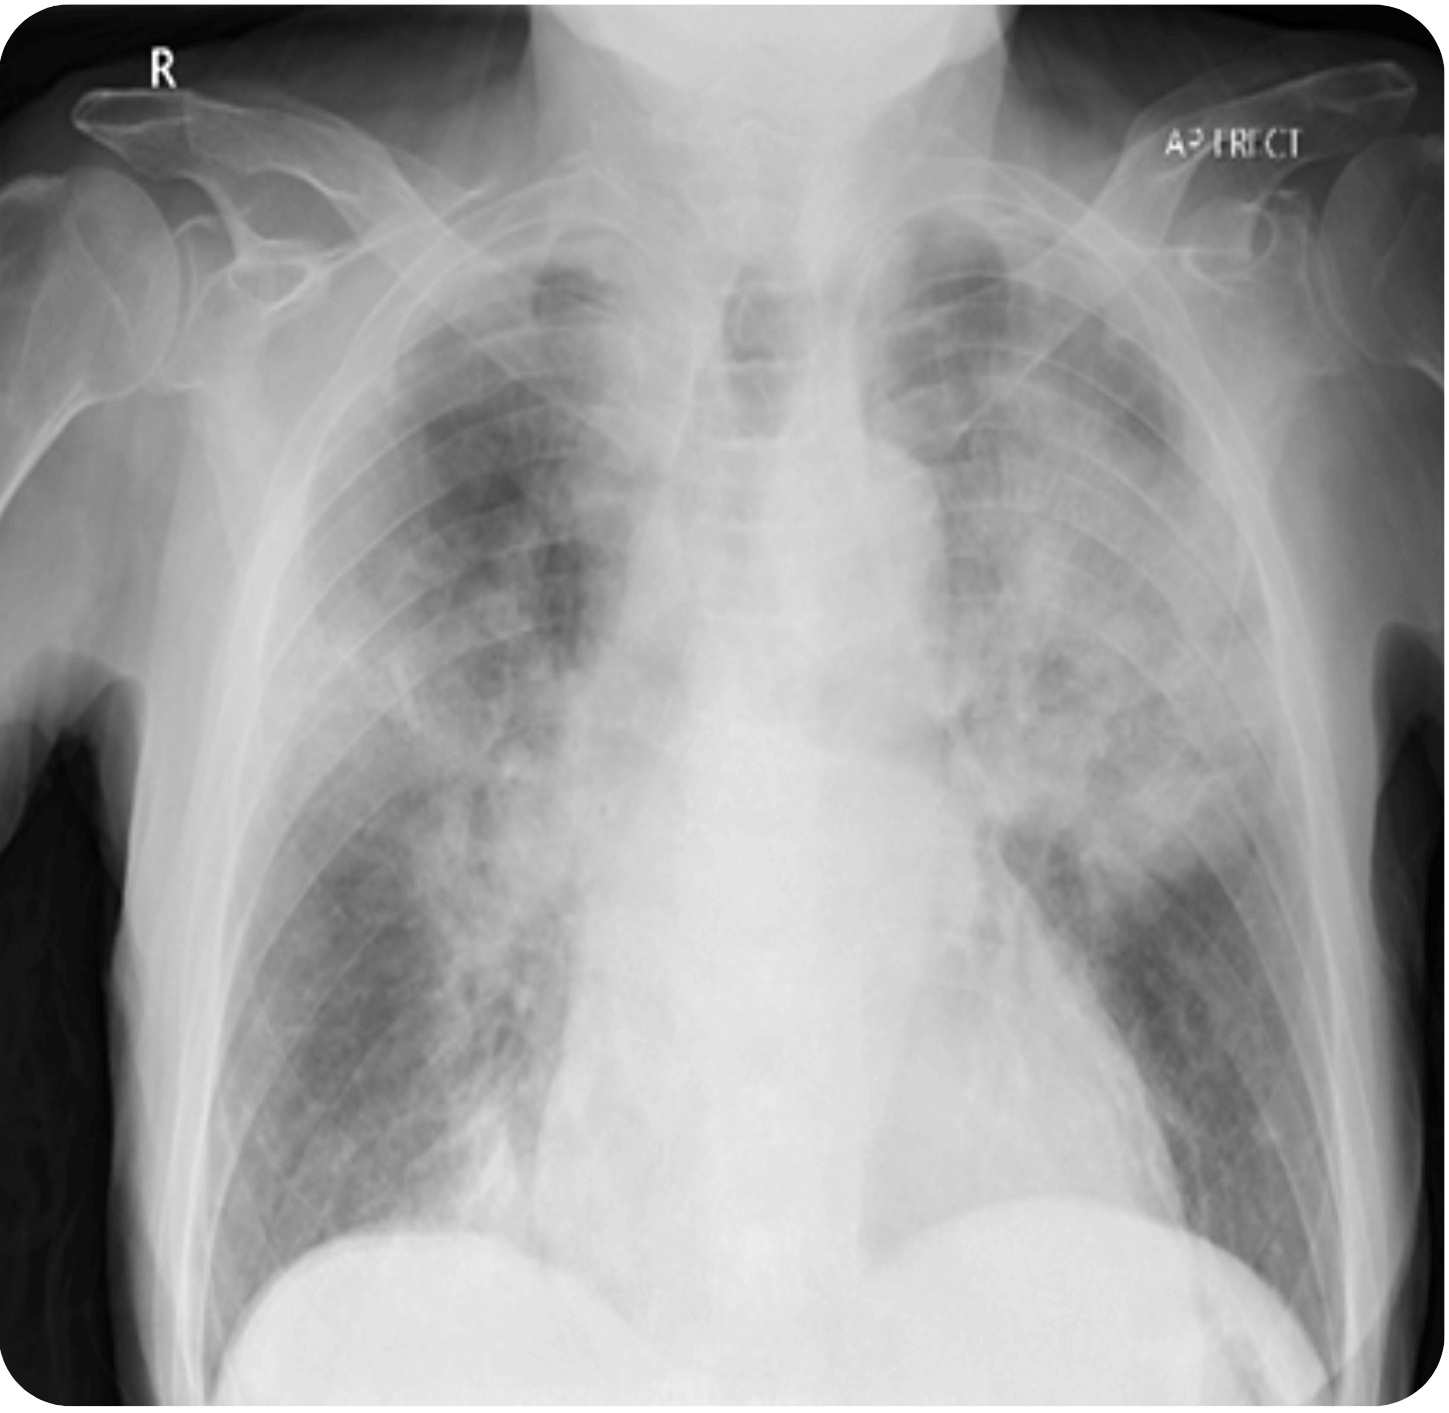

Is Portable Chest X-Ray Effective For Covid-19 Diagnosis . Additionally, cxr utilization for early disease detection may also play a vital role in areas around the world with limited access to reliable. This rapid advice guide examines the evidence and makes recommendations for the use of chest imaging in acute care of adult. However, chest radiography of people who are seriously ill with.

Additionally, cxr utilization for early disease detection may also play a vital role in areas around the world with limited access to reliable. This rapid advice guide examines the evidence and makes recommendations for the use of chest imaging in acute care of adult. However, chest radiography of people who are seriously ill with.

Is Portable Chest X-Ray Effective For Covid-19 Diagnosis This rapid advice guide examines the evidence and makes recommendations for the use of chest imaging in acute care of adult. Additionally, cxr utilization for early disease detection may also play a vital role in areas around the world with limited access to reliable. This rapid advice guide examines the evidence and makes recommendations for the use of chest imaging in acute care of adult. However, chest radiography of people who are seriously ill with.